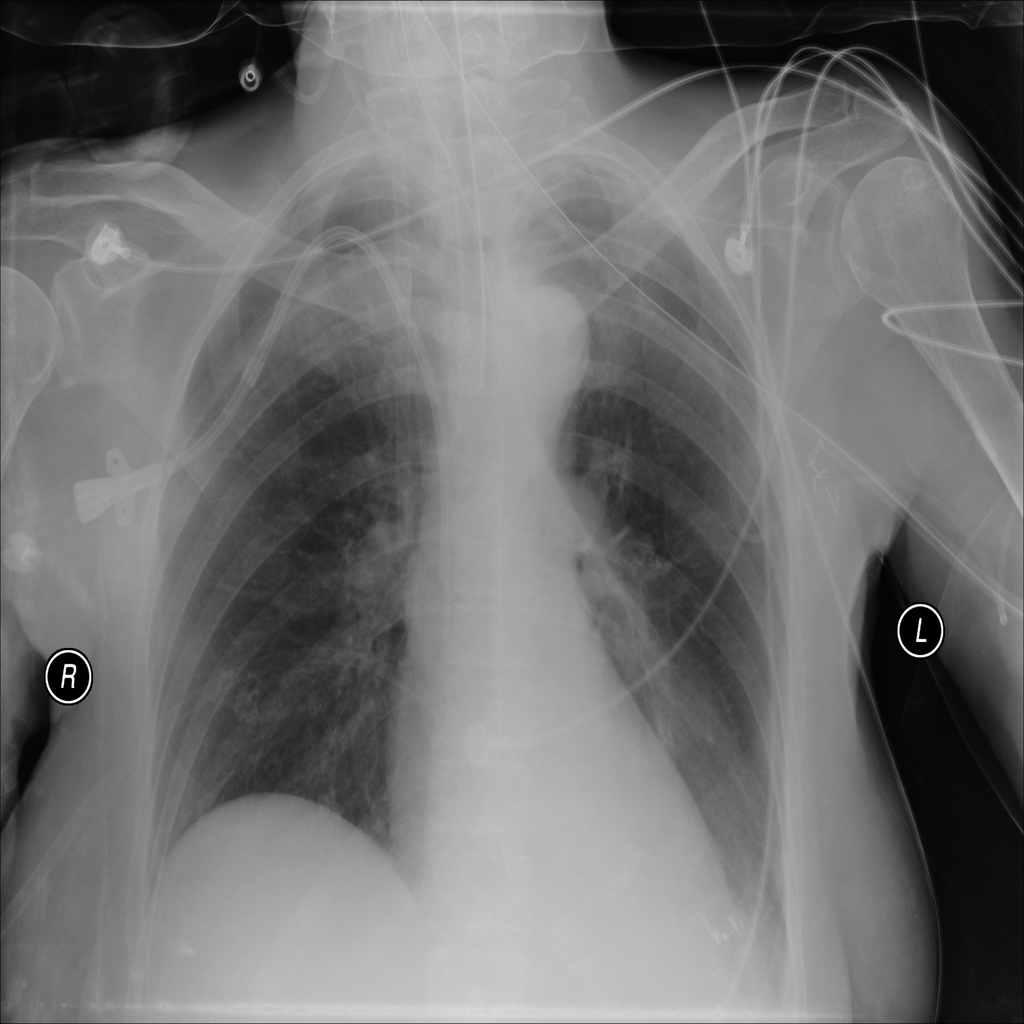

PAT-B3C3 · IMG-001Pneumonia

PAT-B3C3 · IMG-001

PA